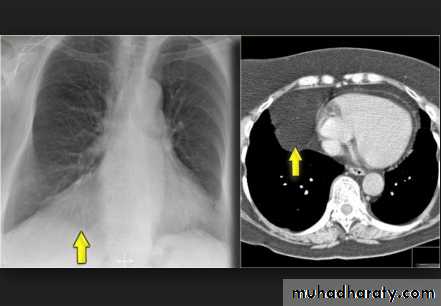

Un complicated Hydatid cyst of th lung , cuased by echenococus granulosis seen as well defined nodule or mass lesion .

Early rupture is sen as a cresnt air sign .ddx aspergillus ball